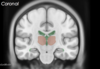

Coronal view of thalamus

- 2 thalami

- Body of lateral ventricles

- 3rd ventricle in middle of 2 thalami

- Inferior horn of lateral ventricle (just about seen in temporal lobe)